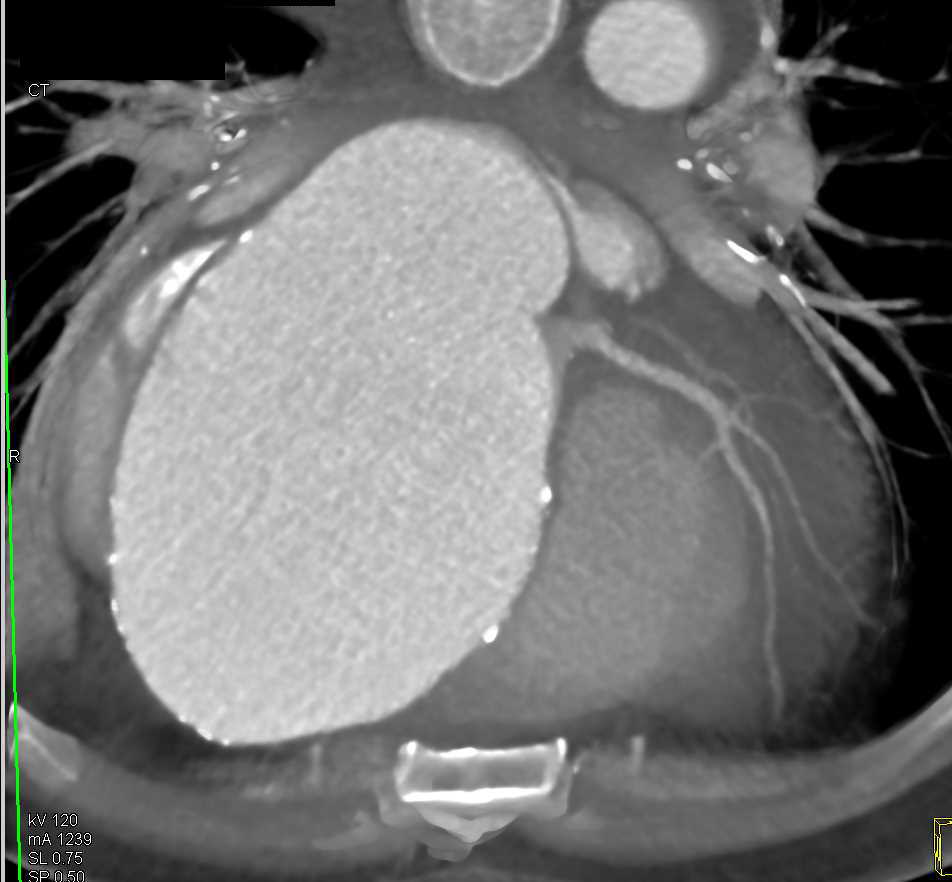

Septic Emboli in a Patient with Pancreatic Cancer